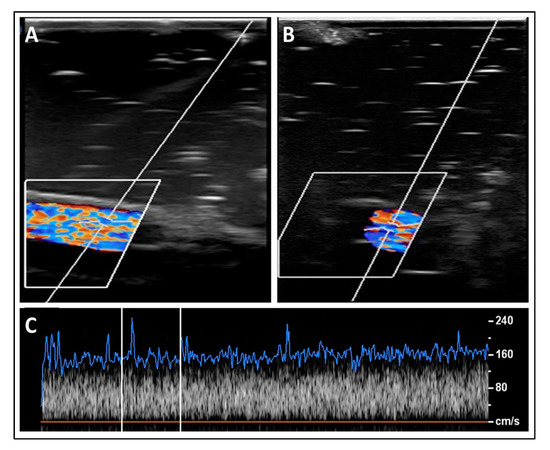

3.2. Experimental Validation of the Proposed Nanotechnology-Based Drug-Delivery System